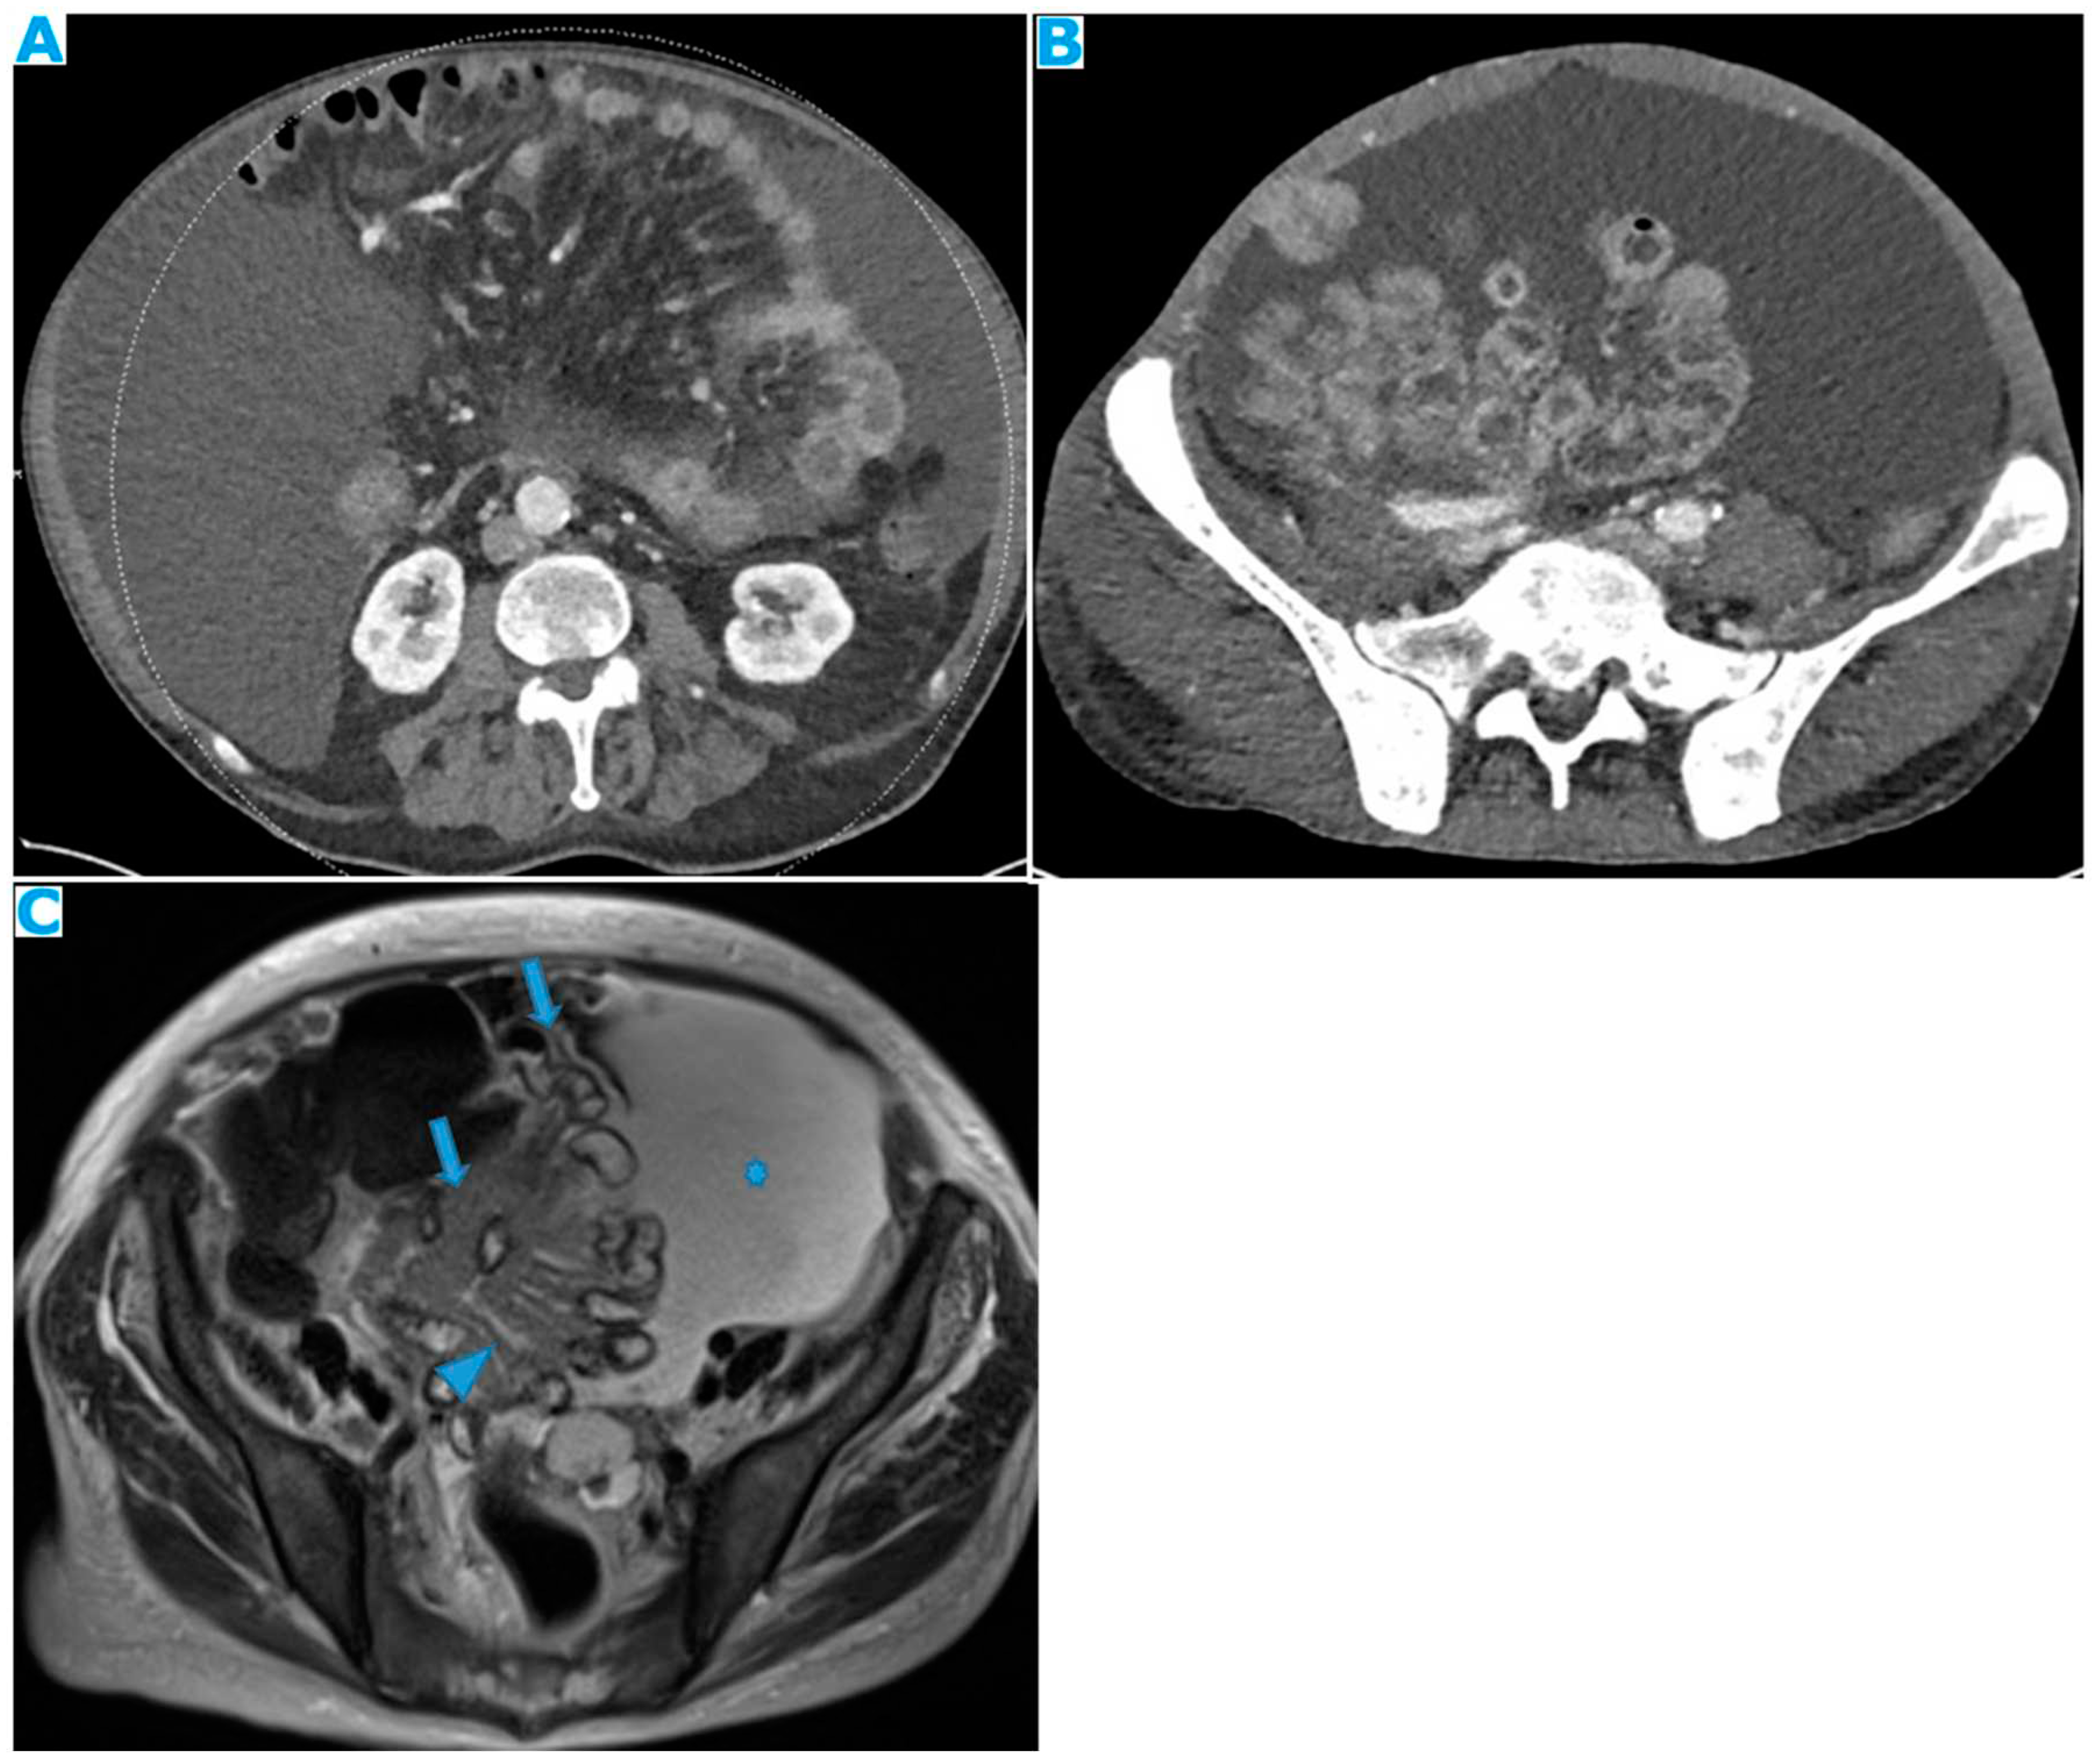

Figure 23.

Axial CE-CT. PC from ovarian carcinoma: mesenteric seeding. Mesenteric involvement may happen as a combination of deposits involving both the mesentery and the bowel serosa, as in this case. Observe the clustered SB loops appearance. The calcified content of some of the deposits enhances their presence (arrow). Omental deposits (*).